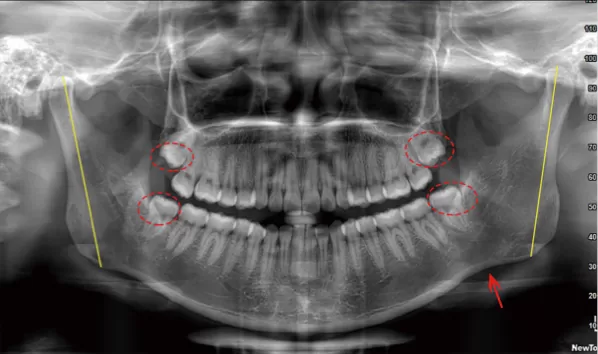

X-rays before treatment

[Panoramic Radiography/Lateral Cephalogram]